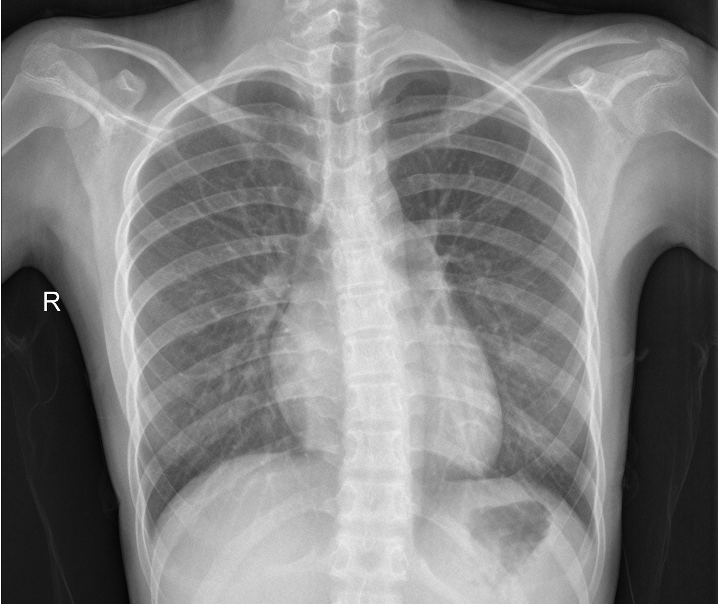

Figure 2 exemplifies two healthy lungs (upper two) and two lungs suffering from pneumonia (lower two). All images of the data set are recorded with different resolutions. Therefore, we convert the images to greyscale and compress them to 128128 pixels. We allocate 1,500 images to the training set, 200 to the validation set, and 1,400 to the test set.